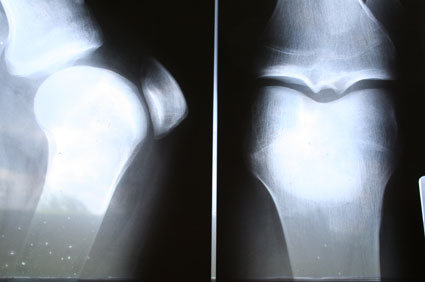

O diagnóstico do “reumatismo” ou doença reumática é eminentemente clínico, dependente da história médica dos pacientes. Os exames de imagem podem confirmar o diagnóstico depois que a doença está bem evoluída. Um diagnóstico diferencial deve ser feito com grande parte das pessoas que sofrem diminuição da flexibilidade e dores nas articulações, sem que isso seja “reumatismo” ou qualquer outra doença inflamatória.